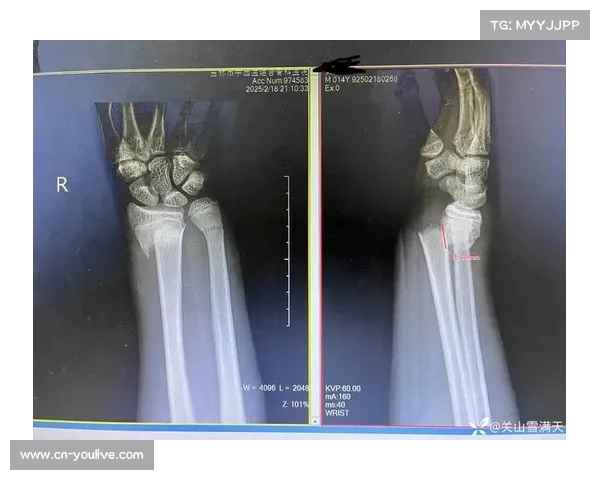

赛后,医疗团队迅速介入,对史密斯进行了初步检查,发现其上下颚均有严重创伤,并伴随颚骨骨折。由于伤势严重,立即将其送往当地医院进行进一步治疗。在医院期间,医生为其进行了详细的影像学检查,并制定了周密的治疗方案,包括手术固定和后续康复计划。